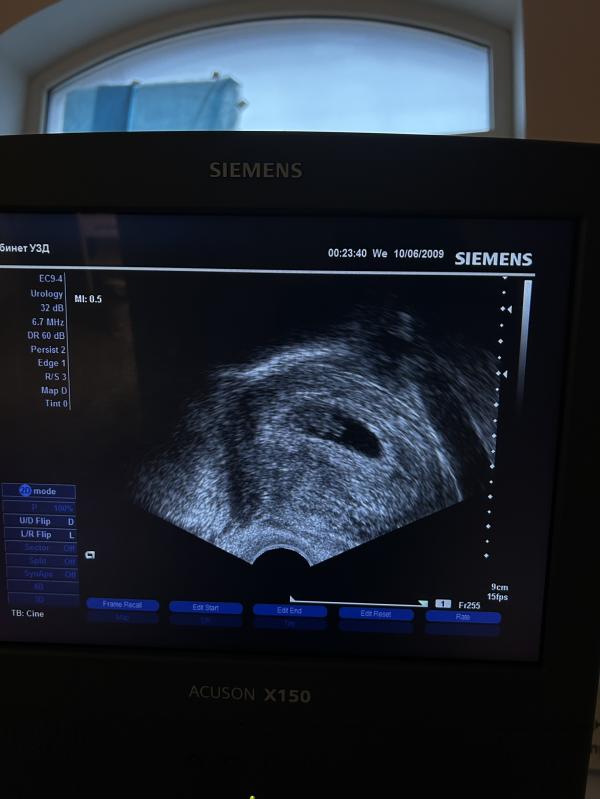

Второе УЗИ при беременности: сердцебиение малыша 125 уд/мин

Вчера были на втором УЗИ

и уже замерили сердцебиение — 125 уд/мин ❤️‍🔥